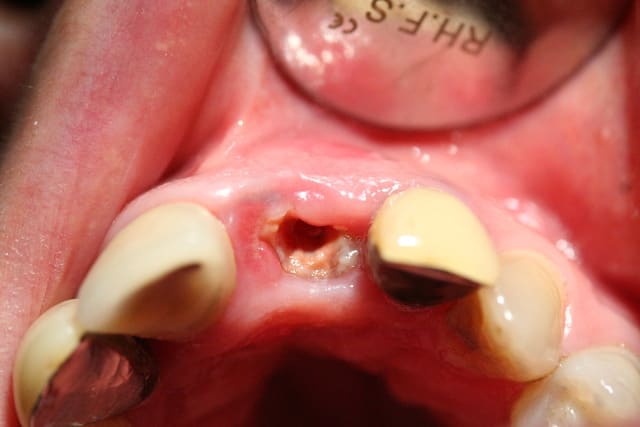

Tout à fait jeamba. Comme tu le dit très justement il n'est pas facile de pouvoir recouvrir la membrane recouvrant ton comblement à moins de :

1- faire un lambeau tracté coronairement (ce qui bride le vestibule et est préjudiciable au niveau antérieur)

2- ou bien faire un conjonctif enfoui (ou pédiculé palatin pour le maxillaire).

Une autre alternative est comme tu le dis d'extraire, d'attendre une cicatrisation des tissus mous (2 à 4 semaines) avant de passer au comblement.

J'ai également trouvé une autre alternative dont je n'ai vu personne d'autre utiliser. Comme vous êtes sympas je vous fait part de ce petit truc utile: prenons l'exemple présenté sur le photos ci jointe où une 22 fracturée doit être extraite. Le principe que j'ai mis au point est de meuler la 22 de facon à enfouir la racine à un niveau sous gingival, quaisiment juxta osseux et d'attendre quelques semaines avant de passer à l'extraction. Cela à pour conséquence un recouvrement radiculaire par les tissus gingivaux. Une fois la racine enfouie, je n'ai plus qu'à ouvrir, extraire au periotome, faire mon comblement si besoin, placer ma membrane et suturer mon lambeau sans avoir à le tracter, ou presque.

> Et que fais-tu comme tempo dans le cas montré ?

J'ai conservé la couronne de la 22 que j'avais séparé de la racine et je l'ai collé aux dents adjacentes. Facile et rapide, il faut juste penser à ne pas comprimer la gencive avec le provisoire.